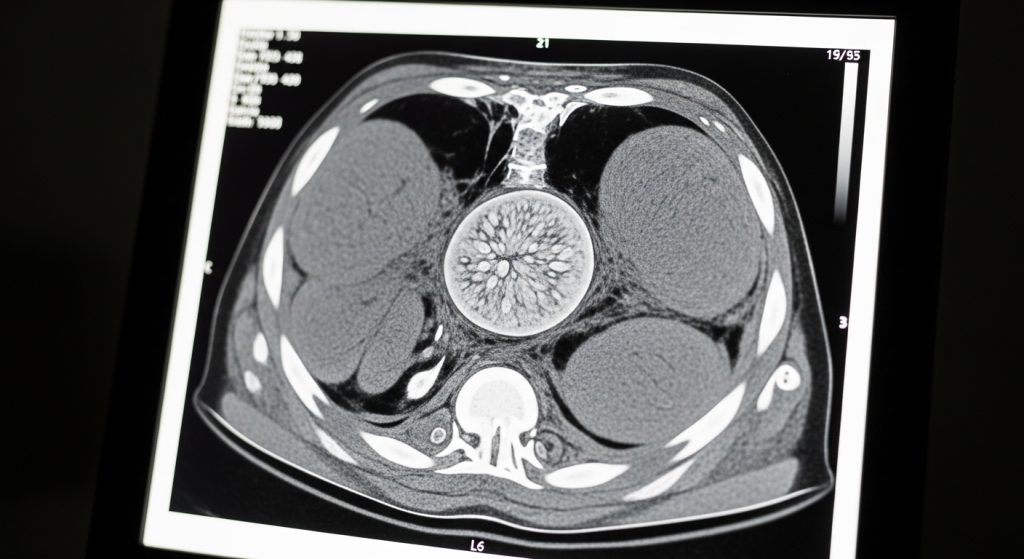

- Imaging, often a high-resolution CT (HRCT) scan to look for scarring patterns

Because patterns can overlap with other lung diseases, some people benefit from a multidisciplinary review (pulmonology, radiology, pathology).